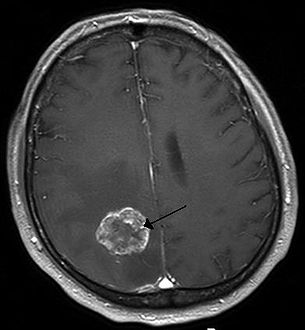

Brain imaging (neuroimaging such as CT or MRI) is needed to determine the presence of brain metastases.[5] In particular, contrast-enhanced MRI is the best method of diagnosing brain metastases, though detection is primarily done by CT.[9] Biopsy is often recommended to confirm diagnosis.[5]

In brain metastasis due to malignant melanoma, MRI imaging showed high T1 and low T2 intensity due to the deposition of melanin in the brain. In susceptibility weighted imaging (SWI), it usually shows abnormal SWI hypointensity in larger proportion than brain metastasis caused by breast carcinoma.[11]